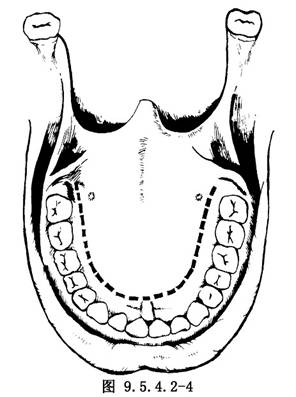

(1)切口:最常採用硬齶U形切口。自一側第3磨牙後端平面開始,切口直達骨膜下,繞向齶大孔內側,再向前大致與牙列平行向前延伸至切牙後1cm處,再彎向對側形成U形切口(圖9.5.4.2-4)。爲了擴大術野,U形切口的一端可移至齶大孔外側,將齶大動脈切斷結紮,也可將切口後端兩側向後外延向舌齶弓,但切不可結紮兩側齶大動脈,以免黏骨膜瓣壞死。在翼突溝外將齶帆張肌切斷,軟齶即可拉向後方(圖9.5.4.2-5)。如腫瘤向翼齶窩擴展,可將切口後端繞過腫瘤一側的上頜粗隆加做頰齦切口(圖9.5.4.2-6)。